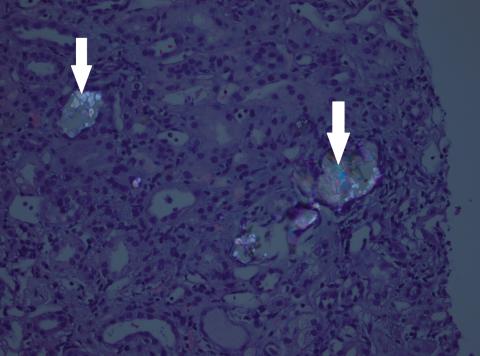

Der ses dobbeltbrydende calciumoxalatkrystaller (pile) i ­tubuli ved polariserende lys. Hæmatoxylin-eosin-farvning. For­størrelse 20 ×.

Der blev udført nyrebiopsi efter tre dage. Biopsien viste svær akut tubulusskade med talrige oxalatkrystaller, hvilket er foreneligt med oxalatnefropati.